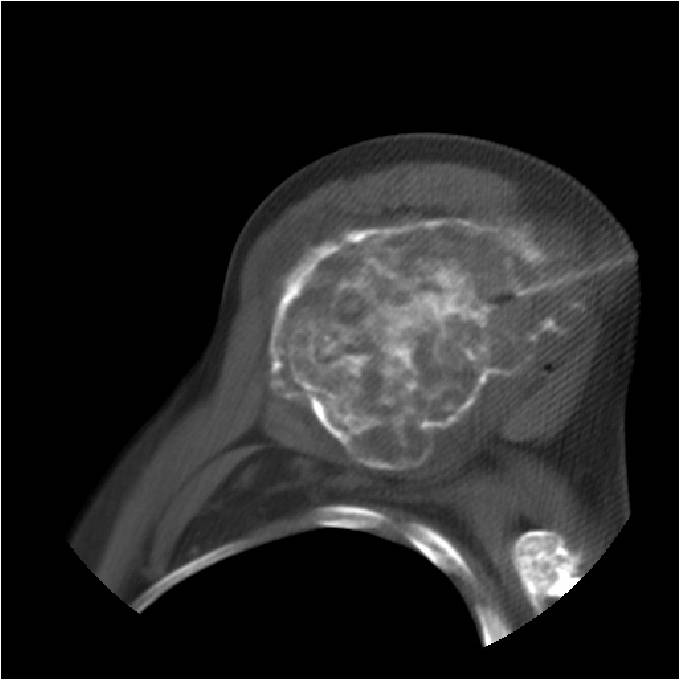

- MRI

- Lobulated margin

- Marked increased intensity long TR images

- Calcified chondroid – low intensity all sequences

MRI:

- Lobulated margin (Lobular Growth Pattern)

- T1 Weighted Images: Intermediate Signal Intensity

- Calcifications will be low signal

- T2 Weighted Images: High Signal Intensity

- High water content shows as high signal on T2 weighted images

- There should never be any cortical destruction nor a soft tissue component. If this exists then the tumor must be a chondrosarcoma.

- Endosteal scalloping and cortical expansion is acceptable for phalangeal tumors. In most benign long bone cartilage tumors there is minimal endosteal scalloping but there should be no cortical expansion nor thickening. There should be no cortical destruction and no soft tissue component associated with an enchondroma. Cortical destruction, periosteal thickening, cortical expansion and a soft tissue component indicates a chondrosarcoma of the long bone.